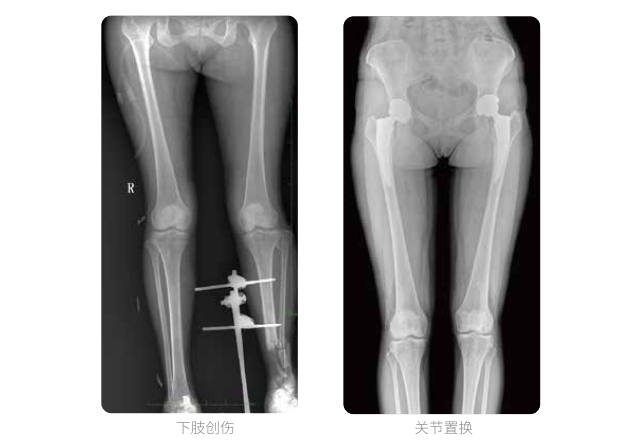

双下肢临床影像

普爱医疗动态数字化X线摄影(动态DR)可以整体显示双髋至双踝关节,直观的展示因关节软骨磨损和软组织不平衡所造成的畸形及力线异常,全面对比了解双下肢的病变情况。对于下肢矫正和人工关节置换术的术前计划,术后观察有着重要的临床意义。